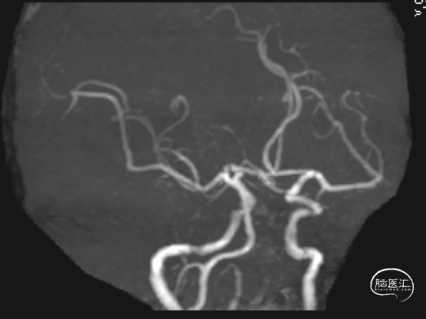

术后头晕呕吐,当日DWI:左侧小脑梗死,MRA未见明显大血管栓塞。

术后第3天患者恶心、呕吐症状消失,仍有头晕,复查DWI及MRA。